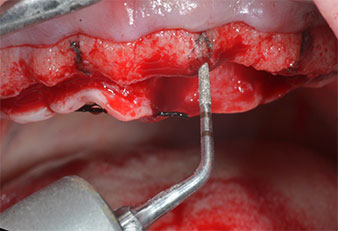

Пиезоелектрически инструмент с диамантено покритие с форма на пламък (Piezomed I1) e използван за маркиране на позициите на имплантите и за пилотна подготовка (Фиг. 3). Препарацията беше извършена с внимателни вертикални движения, с намалена мощност, пълна иригация и лек натиск (под 300 g) След това се приложи пилотен инструмент (Piezomed I2A/ I2P) за първоначално увеличение на диаметъра на имплантното ложе с 2 mm (Фиг. 4), последвано от 3 mm разширение (Фиг. 5)

В случай на твърда кост, цялата поредица от инструменти, включително междинните инструменти Piezomed Z25P и Z35P, трябва да се използват за разширяване на остеотомиите.

Те също така са предназначени за подготовка в близост до синусовата мембрана във връзка с вътрешни аугметационни процедури или когато има по-малко от 4 mm остатъчна височина на костта.

В настоящия случай инструменти Z25P и Z35P не са използвани поради сравнително меката задна кост, която лесно се обработва с I3A/I3P.

Поради сравнително твърдата кост (D2) в тази област, 10-милиметровото имплантно ложе в позиции 11 и 21 беше завършено с ротационен дрил с диаметър 4 mm в комбинация с W&H хирургичен обратен наконечник WS-75 L, W&H имплантологичен мотор Implantmed и опционалния W&H Osstell ISQ модул. За разлика от това, благодарение на меката кост, дисталните зони се подготвят до окончателен диаметър 3 mm, използвайки накрайник за Piezomed I3P. Имплантите най-накрая са поставени трансгингивално, за да остеоинтегрират за три месеца (Фиг. 6-10). Съществуващата протеза се фиксира на четирите временни импланта (Фиг. 8).